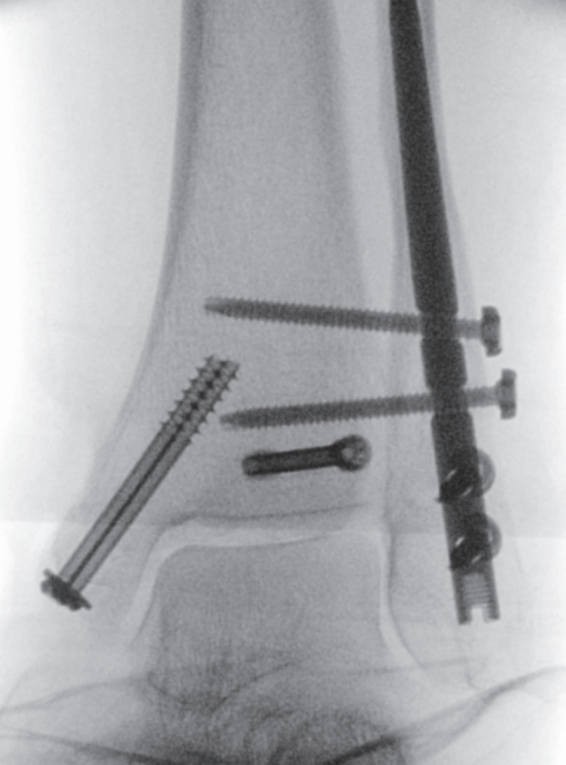

手术技术始于自腓骨尖向远端作短切口。锐性分离皮下组织,置入保护套筒。经套筒将导针置入髓腔并进入近端骨块。用空心开口器开髓,随后依次使用6.1毫米(远端)及3.1毫米、3.6毫米(近端)的钻头进行髓腔扩髓。扩髓过程在透视监控下进行,以避免皮质穿孔并确保钉道居中。将安装于瞄准器的腓骨髓内钉在透视引导下插入至预定深度,向外侧旋转,并用两枚前后向螺钉及两枚三皮质下胫腓联合螺钉锁定。未使用尾帽。最后于多平面进行透视记录(图5a–c)。彻底冲洗并止血后,将胫骨后肌腱复位,修复支持带,采用间断Donati缝合法分层闭合切口。敷以无菌敷料并用背侧夹板固定。

image.png

(a)

(b)

(c)

图 5. (a–c):最终术中透视图像:(a) 前后位视图,(b) 侧位视图,(c) 踝穴位视图。